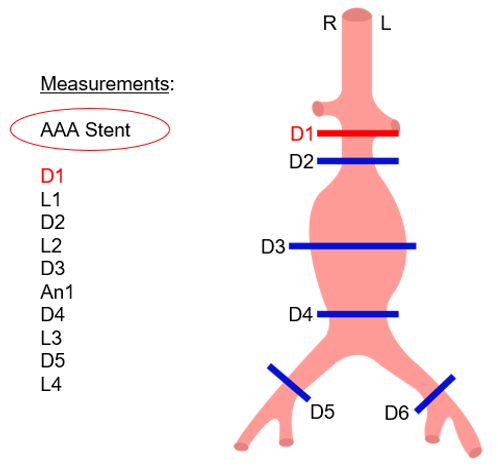

Endoprosthesis Planning

In this step, you can choose and import the type of prosthesis you want. To do so, you have only to click on the list of prosthesis models and select your choice.

Once the model is selected, you have to adjust the measurements as indicated on the template. For each measurement, check the light contour automatically created by the software.